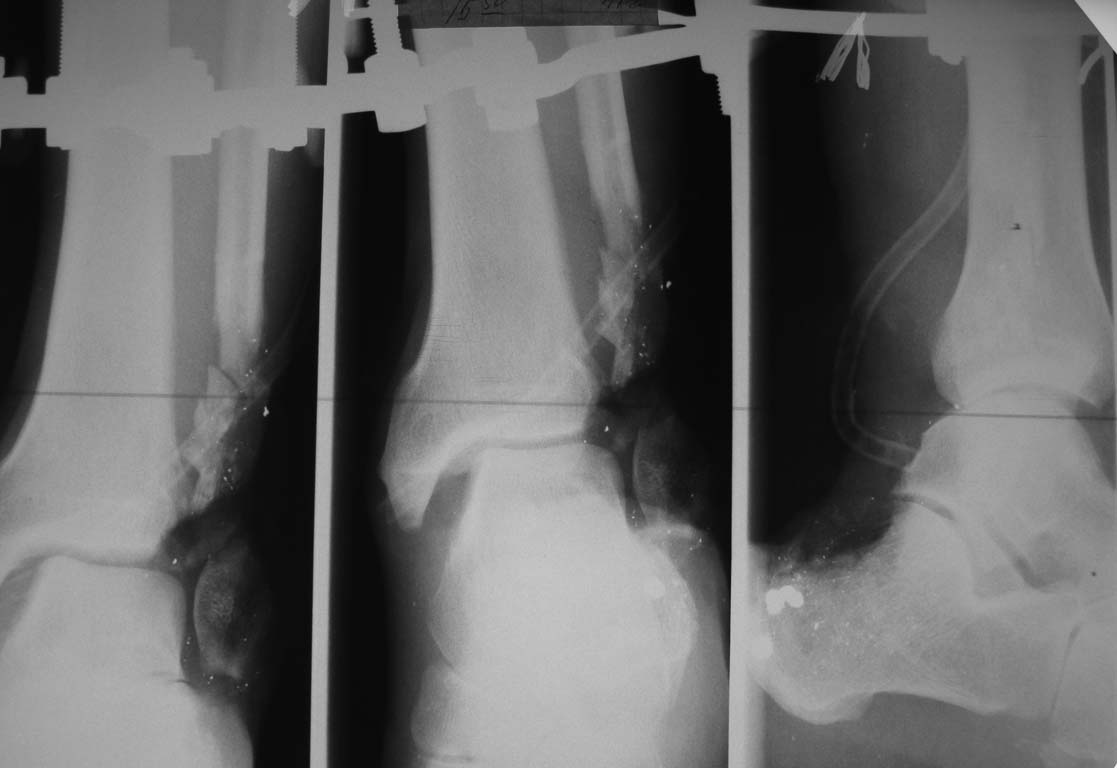

> Уважаемые коллеги, представляется на обсуждение пациент с дробовым

> ранением нижней голени

> в нижней трети.

> Получил ранение при неосторожном обращении с оружием. Доставлен в ЦРБ, где

> выполнено

> ушивание раны и иммобилизация гипсовыми лонгетами. При поступлении нами

> выполнена ПХО раны

> с фиксацией в аппарате. Несколько дней проводилось лечение в повязке с

> низким давлением.

> Рентгенограммы и внешний вид раны представлены во вложенном файле.

> Планируем: выполнить

> артродез голеностопного сустава стержнем с АБ покрытием с замещением

> дефекта задней

> поверхности несвободным лоскутом с противоположной конечности. Использовать

> микрохирургическую технику возможности нет. Хотелось бы услышать мнение

> участников

> форума. Спасибо!